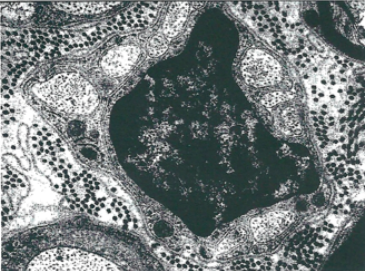

Tracky a écrit:Pour les fibres, la photo (inexistante) représentait une fibre amyélique, donc à noyau central. L'item demande si le noyau est toujours comme sur la photo : central. Faux, dans les fibres myélinisées, non. L'item était général, pas juste sur la photo, ça parait évident.

Bloomwood a écrit:Texto la tutrice : " pour éviter toute ambiguité, dites vous que la fibre est amyélénique". J'ai changé ma réponse suite à cette phrase.

Tout simplement parcequ'à Pasteur on nous a dit : "basez vous sur le fait que la fibre est toujours amyélénique !!" ---- > soit, le noyau toujours central. Donc l'item est D est vrai pour nous .

Texto la tutrice : " pour éviter toute ambiguité, dites vous que la fibre est amyélénique". J'ai changé ma réponse suite à cette phrase.